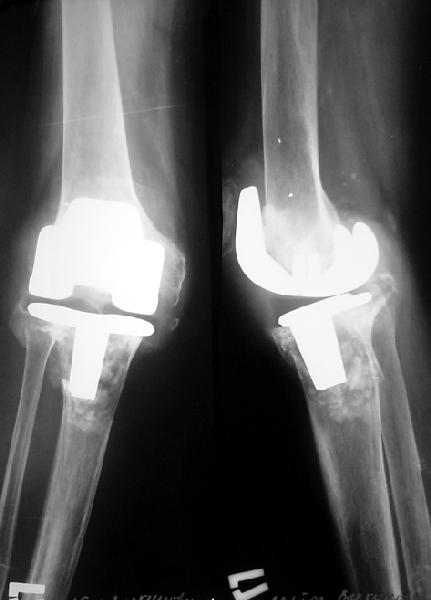

Нестабильный эндопротез колена

Пациентке 1954 г.р. по поводу ревматоидного поражения коленных суставов в 1995 г. выполнено эндопротезирование правого коленного сустава (Biomet AGC); в 1996 г. - компрессионный артродез левого коленного сустава, анкилоз достигнут.

В апреле 2003 г. больная упала, получила перелом на уровне проксимальных метафизов обеих костей правой голени. Имеется клиническая и рентгенологическая картина нестабильности бедренного и большеберцового компонентов эндопротеза. При пункции получено 60 мл серозно-геморрагического отделяемого, посев роста микрофлоры не выявил. Получает глюкокортикоиды per os 5 мг в сут., диклофенак 100 мг/сут. Что можно в данном случае предпринять? Если ревизию, то какую модель протеза лучше испльзовать? Замыкания второго коленного сустава хотелось бы избежать.